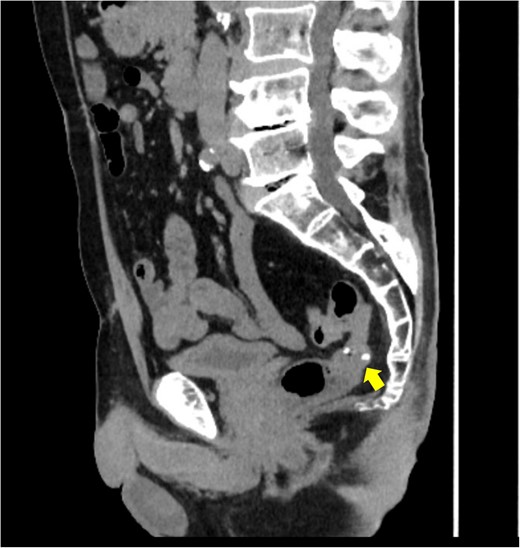

A 72-year-old man diagnosed with NSCLC was referred for possible surgical treatment of a solitary nodule detected in the mesorectum. His medical history included hypertension and endoscopic resection of colonic polyps, with no prior thromboembolism. He had received combined medical treatment for NSCLC (cT4N0M0, stage IIIA) (Fig. 1), including four courses of cisplatin and docetaxel chemotherapy with a 60 Gy/30 fractions radiation dose, followed by 1 year of consolidation therapy with durvalumab (640 mg/body). The patient tolerated the treatment well, achieving a complete response 13 months before presentation (Fig. 2). However, the mesorectal nodule was incidentally discovered during surveillance CT after NSCLC treatment completion. It was round, 15 mm in diameter, showed contrast enhancement, and was near the mesorectal vessels (Fig. 3a and b). An FDG PET/CT scan revealed a solitary mesorectal nodule with an SUVmax of 10.3 (Fig. 4). Consequently, the radiologist suggested differential diagnoses of malignant lymphoma and metastatic lymph nodes from the urinary or lower gastrointestinal tract, as NSCLC typically does not metastasize to mesorectal lymph nodes. No other abnormal FDG uptake was observed. Laboratory tests showed normal levels for tumor markers, including carcinoembryonic antigen, sialyl Lewis X (SLX), squamous cell carcinoma antigen, neuron-specific enolase, cytokeratin fragment (CYFRA), progastrin-releasing peptide, and blood coagulability was within the normal range. Total colonoscopy revealed no neoplastic lesions, and urinary cytology showed nonmalignant urothelial cells. Noninvasive diagnostic approaches, including endoscopic or CT-guided biopsy, were extensively discussed but deemed difficult because of anatomical restrictions, risk of dissemination, and procedure-related complications (such as bleeding or perforation). Because of the potential malignancy and need for en-bloc resection, we opted for surgical resection using a standardized laparoscopically assisted mesorectal excision technique. During rectal dissection, the nodule was not visible through the posterior and lateral sides because it was completely embedded in the mesorectum. Therefore, a Pfannenstiel incision was made in the lower abdomen to exteriorize the rectum after the division of the proximal colon. The nodule was confirmed by direct palpation, marked with a stitch, and subsequently removed after intracorporeal transection of the distal rectum. We inspected the resected specimen and confirmed that the nodule was incorporated (Fig. 5a and b). A colorectal anastomosis was then performed using a double-stapling technique with a circular stapler. The postoperative course was uneventful, except for a slight elevation of the d-dimer level (up to 3.26 μg/ml) on postoperative Day 7, which normalized spontaneously without intensive anticoagulation therapy. The patient was discharged on postoperative Day 10. Pathological examination revealed that the 7-mm white nodule was an intravenous organized thrombus in the mesorectum surrounded by granulation tissue, with no malignancy observed (Fig. 6a and b). Postoperatively, the patient did not require additional chemotherapy or anticoagulation therapy. During the 16-month follow-up, no radiological evidence of NSCLC recurrence and thromboembolism was detected (Fig. 7).

Surveillance computed tomography (CT) image of the pelvis at 16 months postoperatively. No lesions were observed in the mesorectum. The arrow indicates the staples used at the colorectal anastomosis.